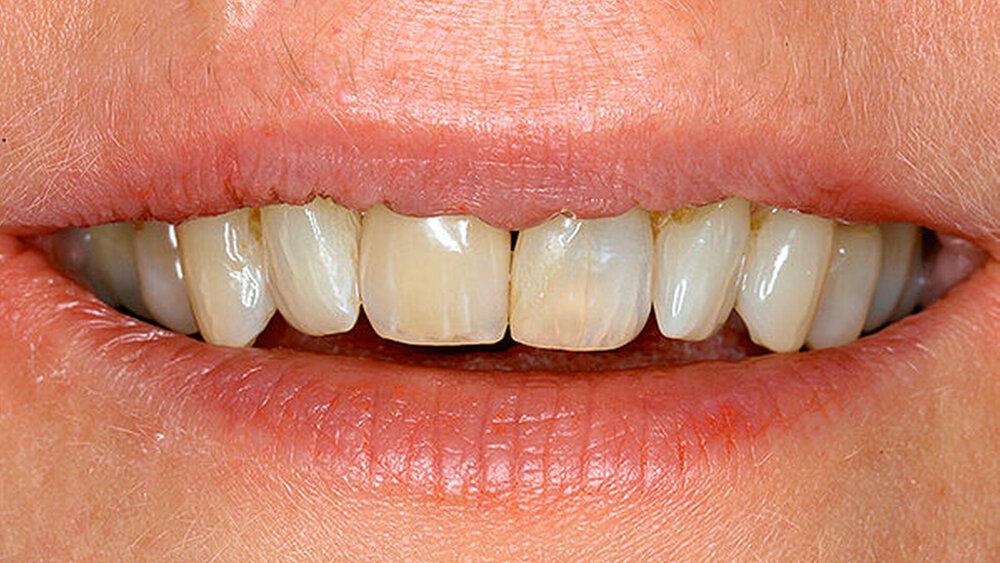

Sind dann auch eher Sofortversorgungsprotkolle umzusetzen?Hermann:Die erzielte Primärstabilität ist in den meisten Fällen so hoch, dass eine sofortige provisorische Versorgung/Belastung möglich ist. Somit können wir unseren Patienten effiziente Behandlungsabläufe anbieten. Die Effizienz zeigt sich beispielsweise auch bei der Reduktion der Bohrschritte durch ein flexibles Bohrprotokoll. Gerade im weichen Knochen benötigen wir meist nur drei Bohrschritte bis zur Insertion des Implantats und erzielten eine exzellente Primärstabilität durch eine geringere Aufbereitung des Implantatbetts. Auf den zusätzlichen Einsatz nicht-ablativer Techniken (Osteotome) kann häufig verzichtet werden. Ein Teil der 80 von uns gesetzten PROGRES ‧ SIVE- ‧ LINE Implantate befindet sich bereits in der prothetischen Nachkontrolle. Das klinische und prothetische Outcome ist hervorragend. Es gibt weder chirurgische Komplikationen noch Probleme bei der Einheilung, und die prothetische Versorgung funktioniert perfekt.

Ihr Fazit? Hermann:Zusammenfassend kann ich sagen, dass wir mit der CAMLOG PROGRESSIVE-LINE eine Erweiterung der klinischen Indikationen in Bezug auf eine simultane Vorgehensweise (Implantation und Augmentation kombiniert) beobachtet haben, und zwar aufgrund der bereits erwähnten Primärstabilität bei schwierigen anatomischen Situationen. So können wir in vielen Fällen auch eine Sofortversorgung/Sofortbelastung des Implantats in Erwägung ziehen. Die situative Adaptation des Bohrprotokolls verschafft uns eine effiziente Insertion, die vorhandene, bewährte Prothetikschnittstelle der Implantate von CAMLOG das vertraute Handling, und dies alles bei einem Implantat, das wir bei allen klinischen Situationen zum Einsatz bringen konnten.